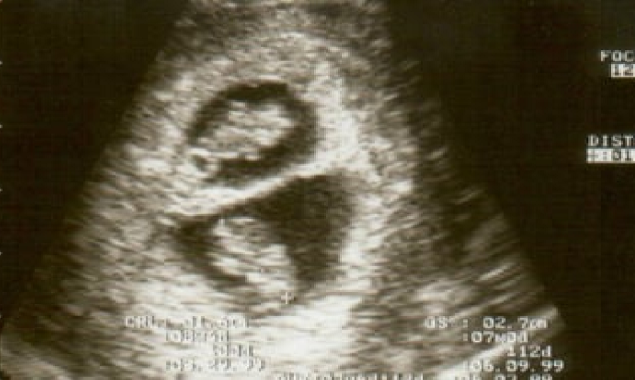

لیکن پھر ڈاکٹر نے انہیں ایک انتہائی حیران کن خبر سنائی، کہ وہ ایک نہیں بلکہ دو بچے ہیں، اور اوڈالس کا ایک ہی ہفتے میں مختلف اوقات میں دو بار حمل ٹھہرا ہے۔

دوہرا حمل، جسے بصورت دیگر “سپرفیٹیشن” کے نام سے جانا جاتا ہے، انتہائی نایاب ہے۔

سپرفیٹیشن سے مراد ایسی صورت حال ہے جہاں ایک عورت پہلے سے جاری حمل کے دوران دوسری بار بھی حاملہ ہو جاتی ہے۔